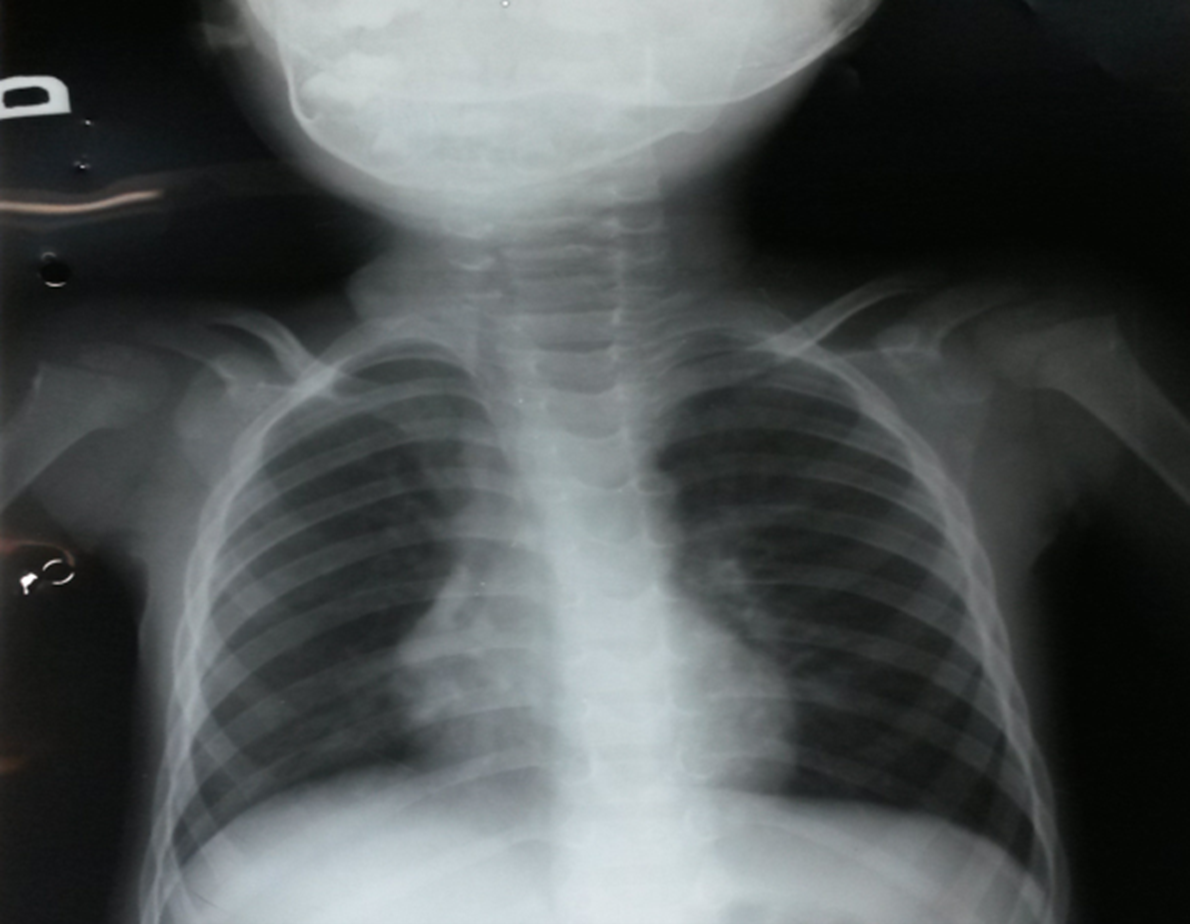

Right Aortic Arch and Arterial Flow Steal: Case Report

Luciana Yukie Nakagawa, Ana Caroline de Mélo Viana, Maria de Fatima de Lira Silva, Adriene Gonçalves Mota, Renan de Lima Rocha, Marcelo Calil Burihan, Renata Nunes da Silva

bjcr113